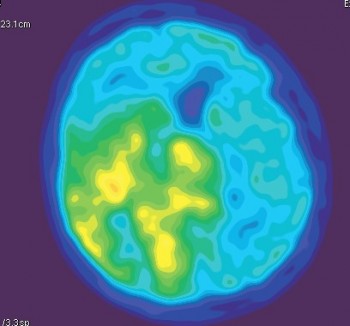

Что такое астроцитома на ПЭТ-КТ: диагностика и лечение